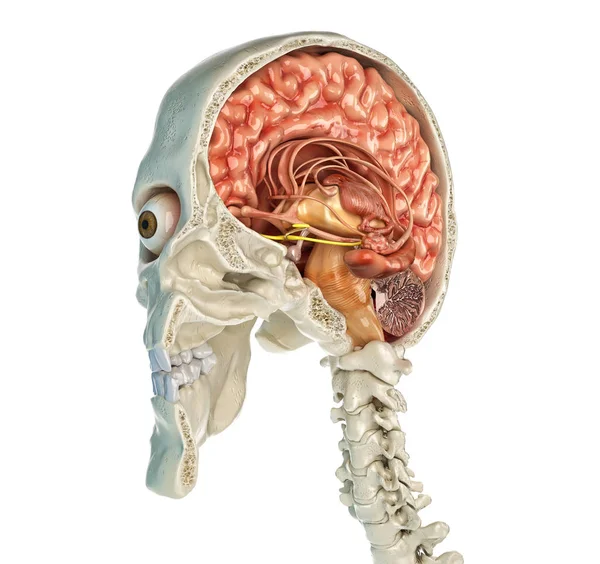

Brains Fact Sumsum Tulang Belakang Terletak Di Dalam

Brains Fact Sumsum Tulang Belakang Terletak Di Dalam